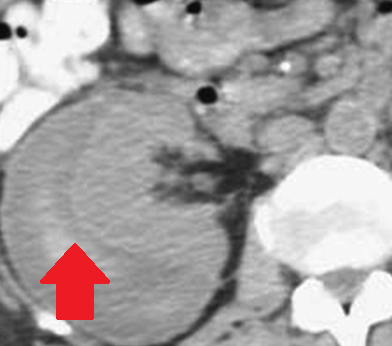

Αυτόματη ρήξη/αιμορραγία νεφρού — αγγειομυολίπωμα (Ευγενική παραχώρηση Dr. V. Penopoulos)